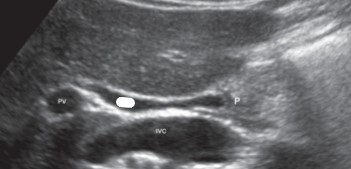

This image was taken in what plane?

Explain your answer.

Sagittal

The pancreas head is the only part visualized